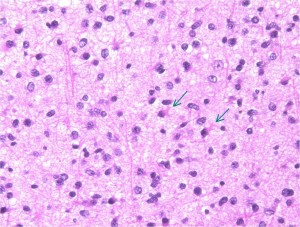

mucoid degenerationを含むprotoplasmic astrocytomaの像です。グレード2の典型的病理像です。

病理は,星細胞に特有の胞体を有しグリア線維が明瞭なびまん性星細胞腫です(クリックすると拡大で見えます)

Ki-67という抗体を使った免疫組織染色でMIB-1 indexというものを見ます。平均で2.5%くらい,高くても4%です。それ以上はグレード3の可能性が高くなります。左の写真のMIB-1の染色率 labling index は3.5%くらいで,グレード2のびまん性星細胞腫としてはやや高い値です。MIB-1染色率が高くなると悪性度が高い傾向にあると考えられます。